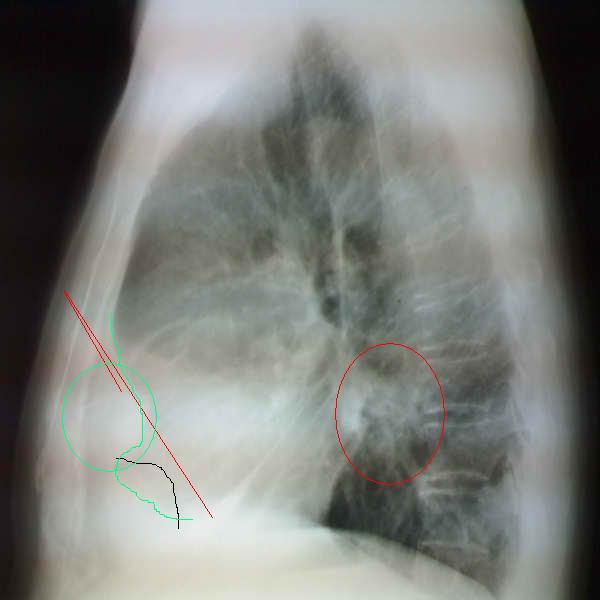

以下是引用李衡钧在2008-6-16 16:46:00的发言:[br]心尖较为陡直,首先考虑冠心病。进一步检查除外室壁瘤。[br]不太像包裹积液和心包囊肿。因为其边缘不是明显锐利清晰。

以下是引用zhangkai在2008-6-16 15:12:00的发言:[br]左下侧胸壁包裹性积液?[br]心脏改变建议结合透视、临床听诊、超声检查排除室壁瘤可能。